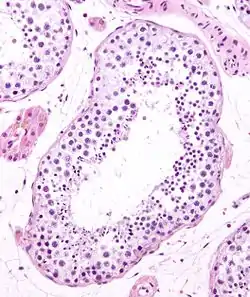

Seminiferous tubule

Seminiferous tubules are located within the testes, and are the specific location of meiosis, and the subsequent creation of male gametes, namely spermatozoa.

![]() Seminiferous tubule in cross-section (large tubular structure – center of image) with sperm (black, tiny, ovoid bodies furthest from the outer edge of the tubular structure). H&E stain. | |

The epithelium of the tubule consists of a type of sustentacular cells known as Sertoli cells, which are tall, columnar type cells that line the tubule.

In between the Sertoli cells are spermatogenic cells, which differentiate through meiosis to sperm cells. Sertoli cells function to nourish the developing sperm cells. They secrete androgen-binding protein, a binding protein which increases the concentration of testosterone inside the seminiferous tubules. Embryologically, they also secrete the anti-Müllerian hormone (AMH) necessary for the female Müllerian ducts to regress.